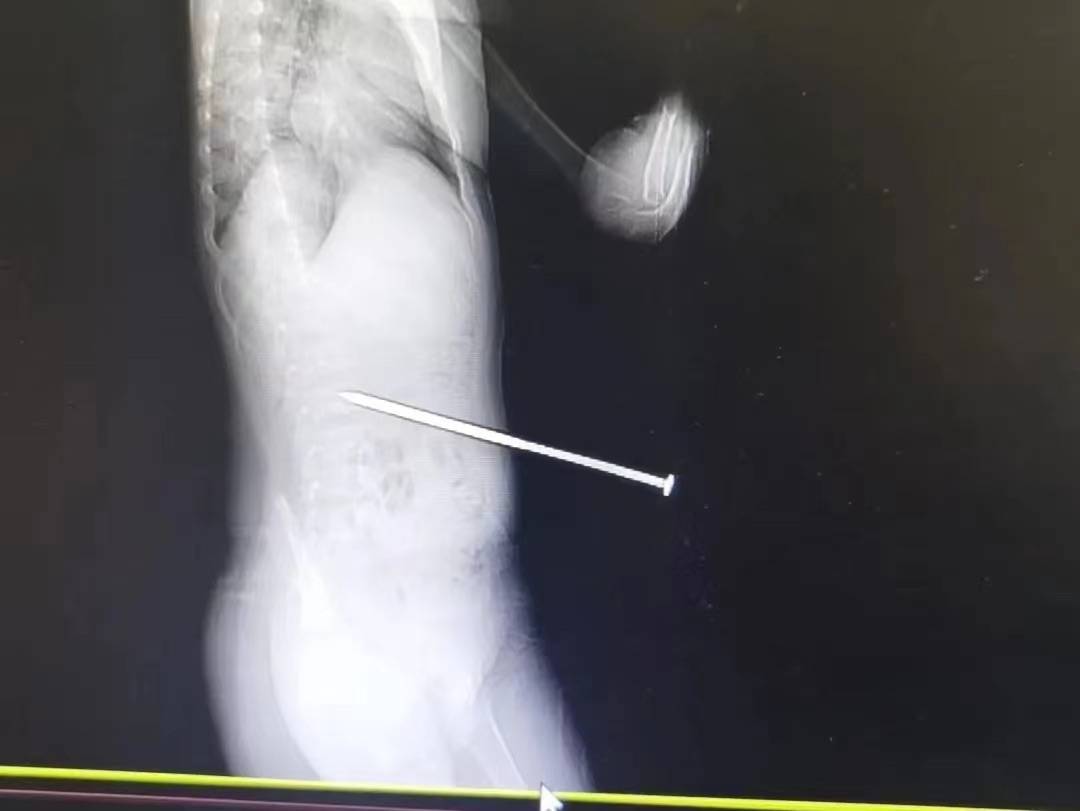

4月9日,杭州一名6岁男孩跟随父母在公园露营时,在草地上玩闹奔跑,不小心被固定帐篷的绳索绊倒,绳索连接的地钉一下子弹出地面,长约12厘米的地钉有6厘米随即扎进了他的腰部。所幸未伤及腹腔,男孩目前已经出院。

图说:长约12厘米的地钉有6厘米扎进男孩腰部,所幸未伤及腹腔。 图源:杭州市卫生健康委